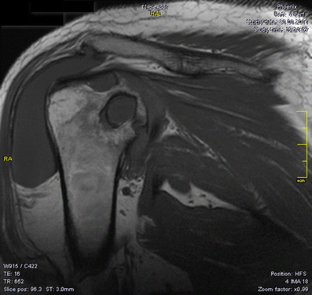

Pigmented villonodular synovitis (PVNS) is a rare, benign proliferative disease of the synovial tissue that affects a single joint or a tendon sheath. Data from the literature present only a few cases of multifocal PVNS. This paper presents multifocal PVNS in the adult. This disease can affect bilateral shoulders, hips and knees. The diagnosis may be delayed by the slow evolution of the disease (up to ten years); some patients may be seen with late-stage degenerative joints, serious complications, painful and functionally uncompensated, with significant locomotion deficit. PVNS requires a radical treatment with prosthetic arthroplasty associated with synovectomy. Complex imaging (X-Rays, magnetic resonance imaging (MRI), ultrasound) and macroscopic appearance of the lesions during surgery confirms the clinical diagnosis of multifocal PVNS with secondary bone lesions. Histology marks the final diagnosis of multifocal PVNS. The postoperative results are good, with recovery in functional parameters of the joints with endoprosthesis.